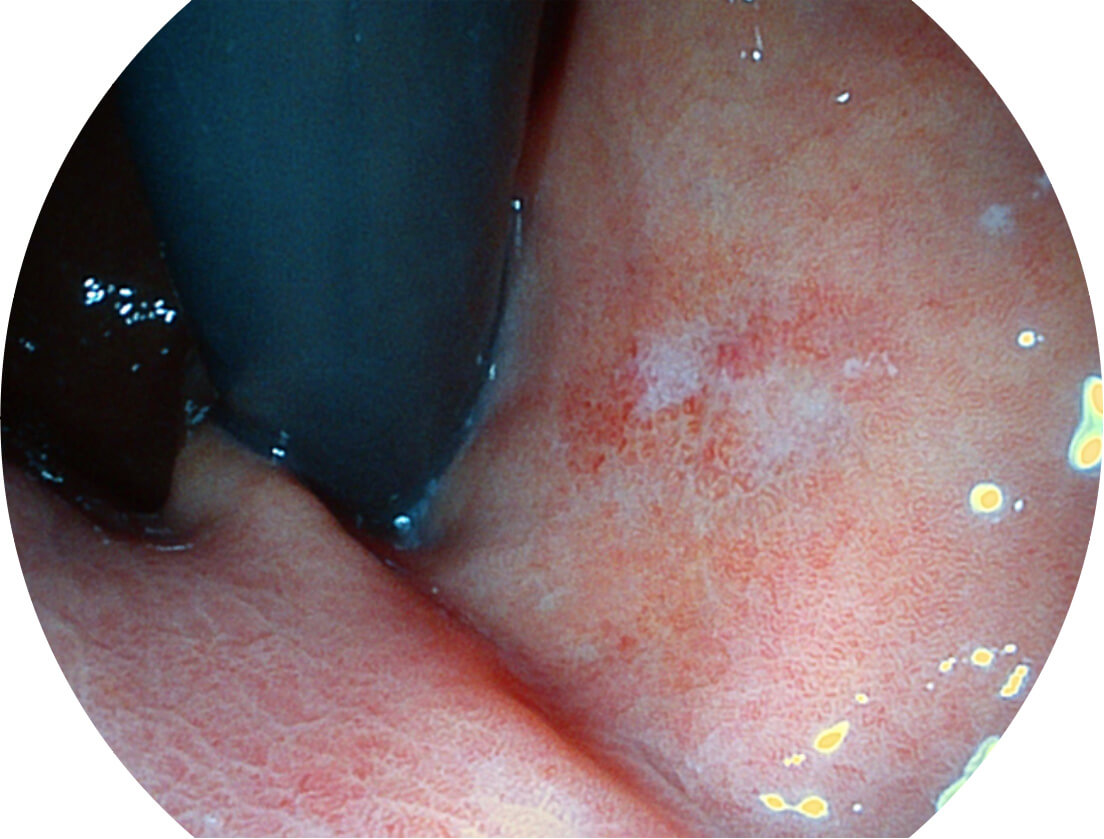

光电复合染色成像技术

Versatile Intelligent Staining Technology, VIST

强调浅层黏膜结构的同时,保证照明亮度和提升浅层微血管与中层血管颜色对比度,病变边界更清晰。

• 白光图像 VIST图像